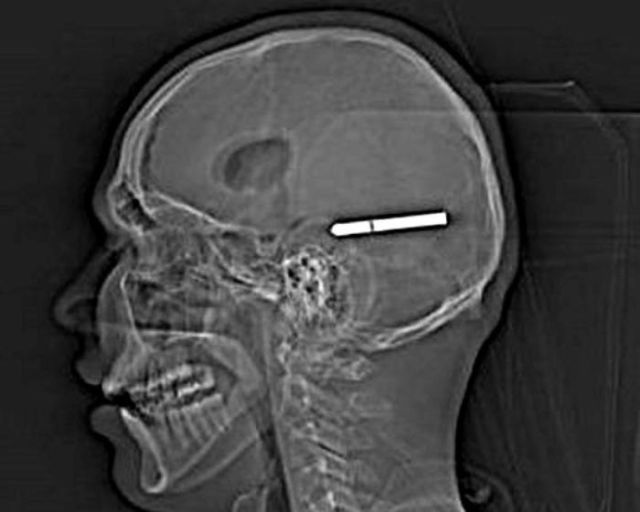

These x-rays will make you wonder how this could ever have happened in the first place.